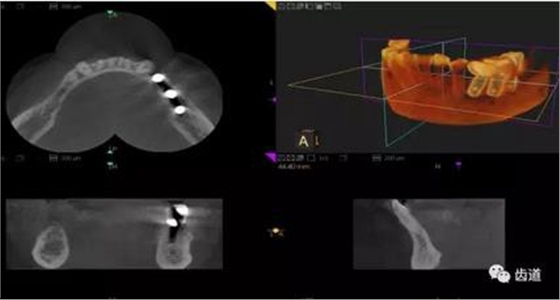

三)種植修復(fù)

CBCT在牙種植修復(fù)中的應(yīng)用。種植前利用CBCT對患者的牙床進(jìn)行檢查,可精準(zhǔn)判斷牙槽骨的寬度、厚度及高度、骨的密度、重要的顏面神經(jīng)、血管和鼻竇位置等。臨床醫(yī)生不僅可以在計(jì)算機(jī)直觀的看到牙槽骨的立體影像,還可以切換不同的視角來觀察硬組織之間的位置關(guān)系,在手術(shù)方案中避開危險(xiǎn)區(qū)域,保證手術(shù)的安全性。臨床醫(yī)生還可以利用CT數(shù)據(jù)進(jìn)行數(shù)字模型重建,配合軟件預(yù)先做好手術(shù)模板,使種植手術(shù)更安全快捷,避免在種植手術(shù)過程中不慎破壞神經(jīng)、鼻竇等解剖結(jié)構(gòu),導(dǎo)致顏面神經(jīng)麻痹、鼻竇炎等并發(fā)癥的發(fā)生。

1、下頜骨種植牙前測量準(zhǔn)備影像

2、上頜骨種植牙前準(zhǔn)備影像

3、下頜骨種植牙術(shù)后